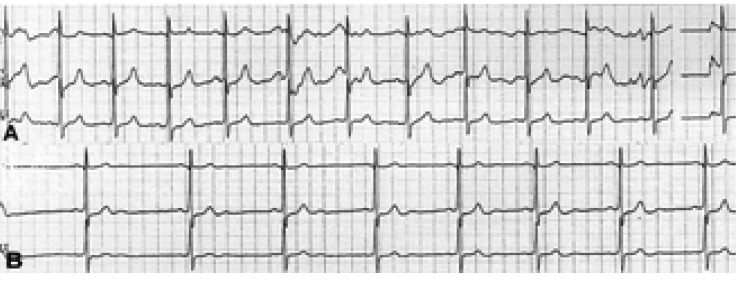

(A) Holter monitoring immediately following the ingestion of a cup of beer (Case 1). The patient had a 7.2-second sinus pause. (B) Electrocardiogram monitoring of the challenge test with a carbonated beverage (a soda pop). The sinus bradycardia caused by the first sip of a soda pop turned into a sinus arrest for 5.4 seconds after the second sip.